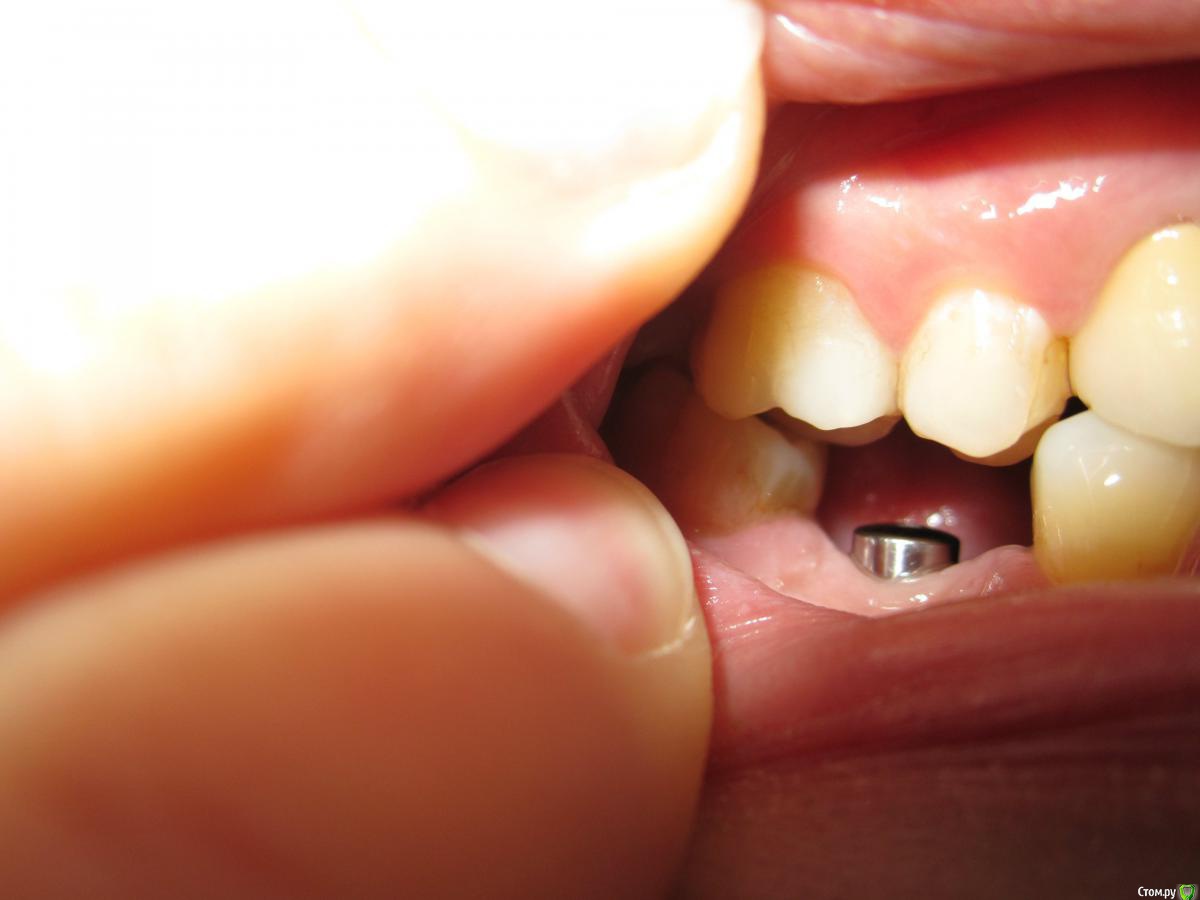

Тая.А Опубликовано 21 февраля, 2015 Поделиться Опубликовано 21 февраля, 2015 Здравствуйте, уже года 2 стоит имплантант только с формирователем, в общем до коронки дело так и не дошло. Врачи говорят имплант стоит хорошо, на рентгене тоже с ним все ок пока,ничего не беспокоит,гигиена соблюдается, формирователь чистится на отлично.Вопросы: - что будет дальше, если так все и оставить,полезут ли верхние и рядом стоящие зубы в разные стороны? - забиваются ли всякие микробы в дырку формирователя? - для того, чтобы десна плотно облегала коронку и никакие остатки пищи не попадали под коронку, нужно наращивать УЗКУЮ десну или делать узенькую коронку? Ссылка на комментарий

SDC Опубликовано 21 февраля, 2015 Поделиться Опубликовано 21 февраля, 2015 (изменено) Уже. Седьмой зуб наклонился вперед, а верхний пятый опустился вместе с десной - проследите за контуром шеек зубов.Дальше будет как повезет.Дырка формирователя под отвертку не должна интересовать микробов, а Вас - микробы в дырке формирователя )))Да, для лучшей гигиены и эстетики необходимо увеличение объема десны, но лет 4-5 назад о десне вопросов не возникало - это современная опция. Изменено 21 февраля, 2015 пользователем SDC 3 Ссылка на комментарий

Тая.А Опубликовано 21 февраля, 2015 Автор Поделиться Опубликовано 21 февраля, 2015 скажите, как правильно называется это операция по увеличению объему десны и какой срок заживления перед тем как ставить абатмент и коронку? Ссылка на комментарий